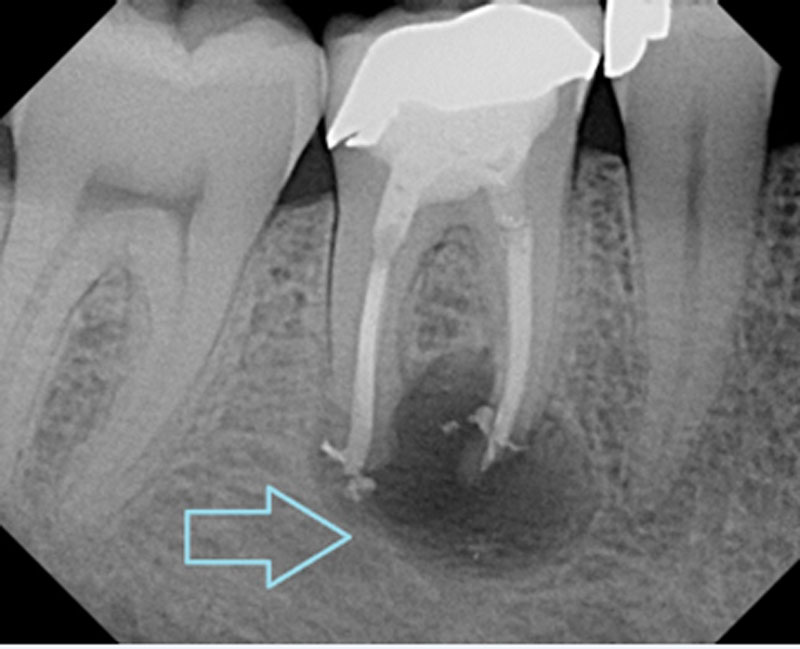

위 엑스레이 사진을 보시면 확실하게 아실 수 있습니다. 큰 검정색 원이 보이시죠? 그게 바로 농양입니다. 일반적인 뼈는 주변처럼 흰색으로 차있습니다. 하지만 위 케이스처럼 검정색이라는건 그 부분이 비어있다는 뜻이고, 무언가 차있다는겁니다. 그게 농양(고름)이구요. 신경치료가 되어있던 치아로 보아, 신경치료 후 염증이 재발한것으로 보입니다. 이런 경우 재신경치료가 필요합니다. (출처: https://www.spokanedental.com/)